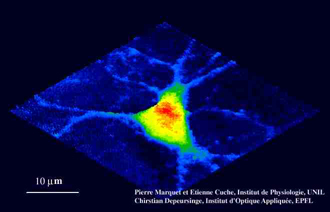

Optical trapping of dielectric spheres